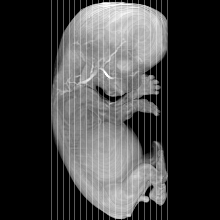

Carnegie Stage 23 (56 post-ovulatory days)

Most embryos at stage 23 are approximately 56-57 postovulatory days old and measure 23-32 mm in length. Distinguishing criteria for this stage include fusion of the eyelids at the medial and lateral margins, clear distinction of the subdivisions of the upper and lower limbs, the forearms appear at or above the level of the shoulders, the superficial vascular plexus of the head is very close to the vertex, and the external genitalia are well developed but not always sufficiently to distinguish the embryo's sex.

(NOTE: These specimens are late stage 23.)

MRI Slice Selector

Mouse: click on a line below to select a view

Finger: tap a line below with a very light touch